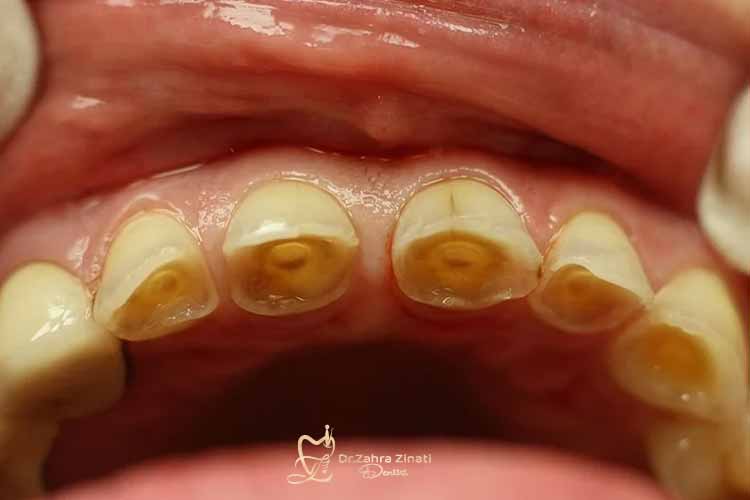

تغییر رنگ و زرد شدن تدریجی دندانها

وقتی مینای دندان نازک میشود، لایه زیرین به نام عاج یا دنتین نمایان میگردد. این لایه رنگی زرد دارد و همین امر باعث تغییر رنگ کلی دندانها میشود. افرادی که به تغییر رنگ حساس هستند، ممکن است تصور کنند که تنها با سفید کردن دندان میتوانند این مشکل را حل کنند؛ اما در حقیقت، دلیل اصلی این زردی، ساییدگی مینا است و روشهای زیبایی بهتنهایی نمیتوانند مشکل را برطرف کنند.

ایجاد ترکهای ریز و لبههای شیشهای روی دندان

مینای ضعیف بهسادگی ترک برمیدارد و لبه دندانها حالت شیشهای یا نیمهشفاف پیدا میکند. این حالت علاوه بر مشکل ظاهری، خطر شکستن یا لبپر شدن دندان را هم بیشتر میکند. در صورت مشاهده چنین تغییراتی، باید جدی گرفته شوند چون بخشی از علائم ساییدگی مینای دندان هستند و میتوانند به مشکلات جدیتر منجر شوند.